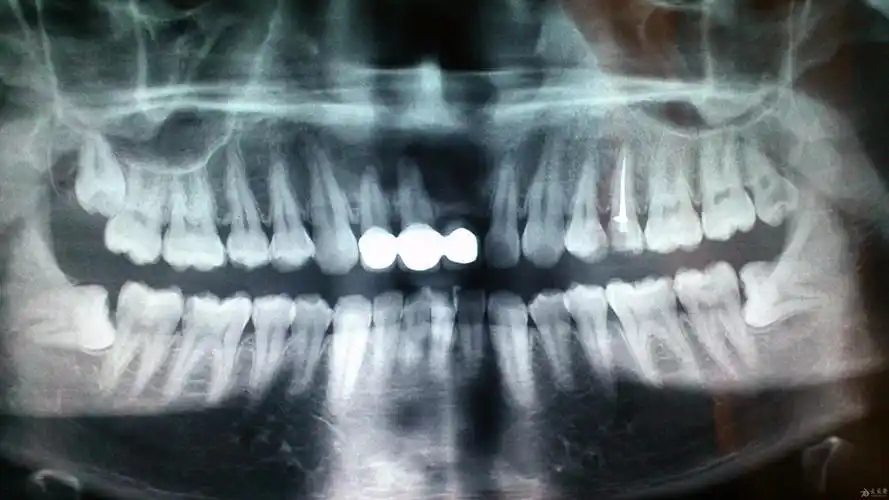

记录口腔保健根尖囊肿根管治疗拔智齿

口腔cbct影像分析根尖囊肿的诊断

看看有没有根尖囊肿 分享到

根尖囊肿了

根尖囊肿